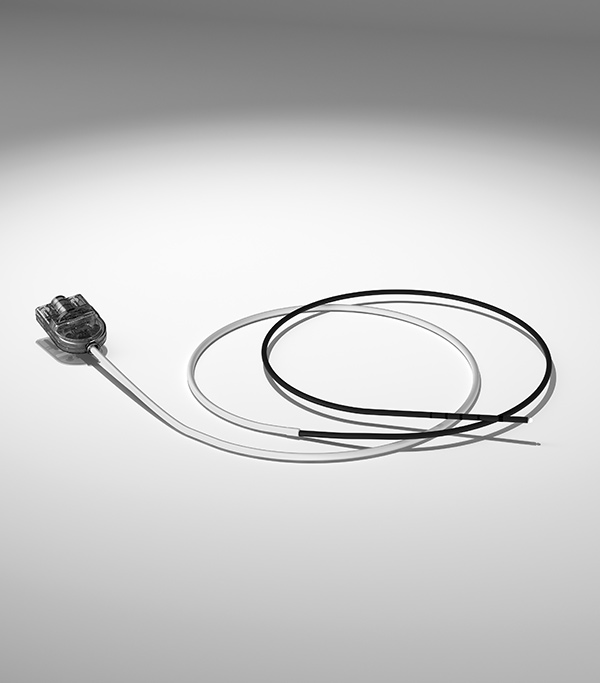

Gewebeablation bei Einwachsen eines Metallstents mit APC 3 unter Verwendung der FiAPC® -Sonde 2200A im forcedAPC Modus

Gezielte Therapie bei Strahlenproktitis mit der FiAPC-Sonde, APC 3 und VIO® 3 unter Verwendung des preciseAPC Modus

Ablation des Barrett-Ösophagus mit HybridAPC